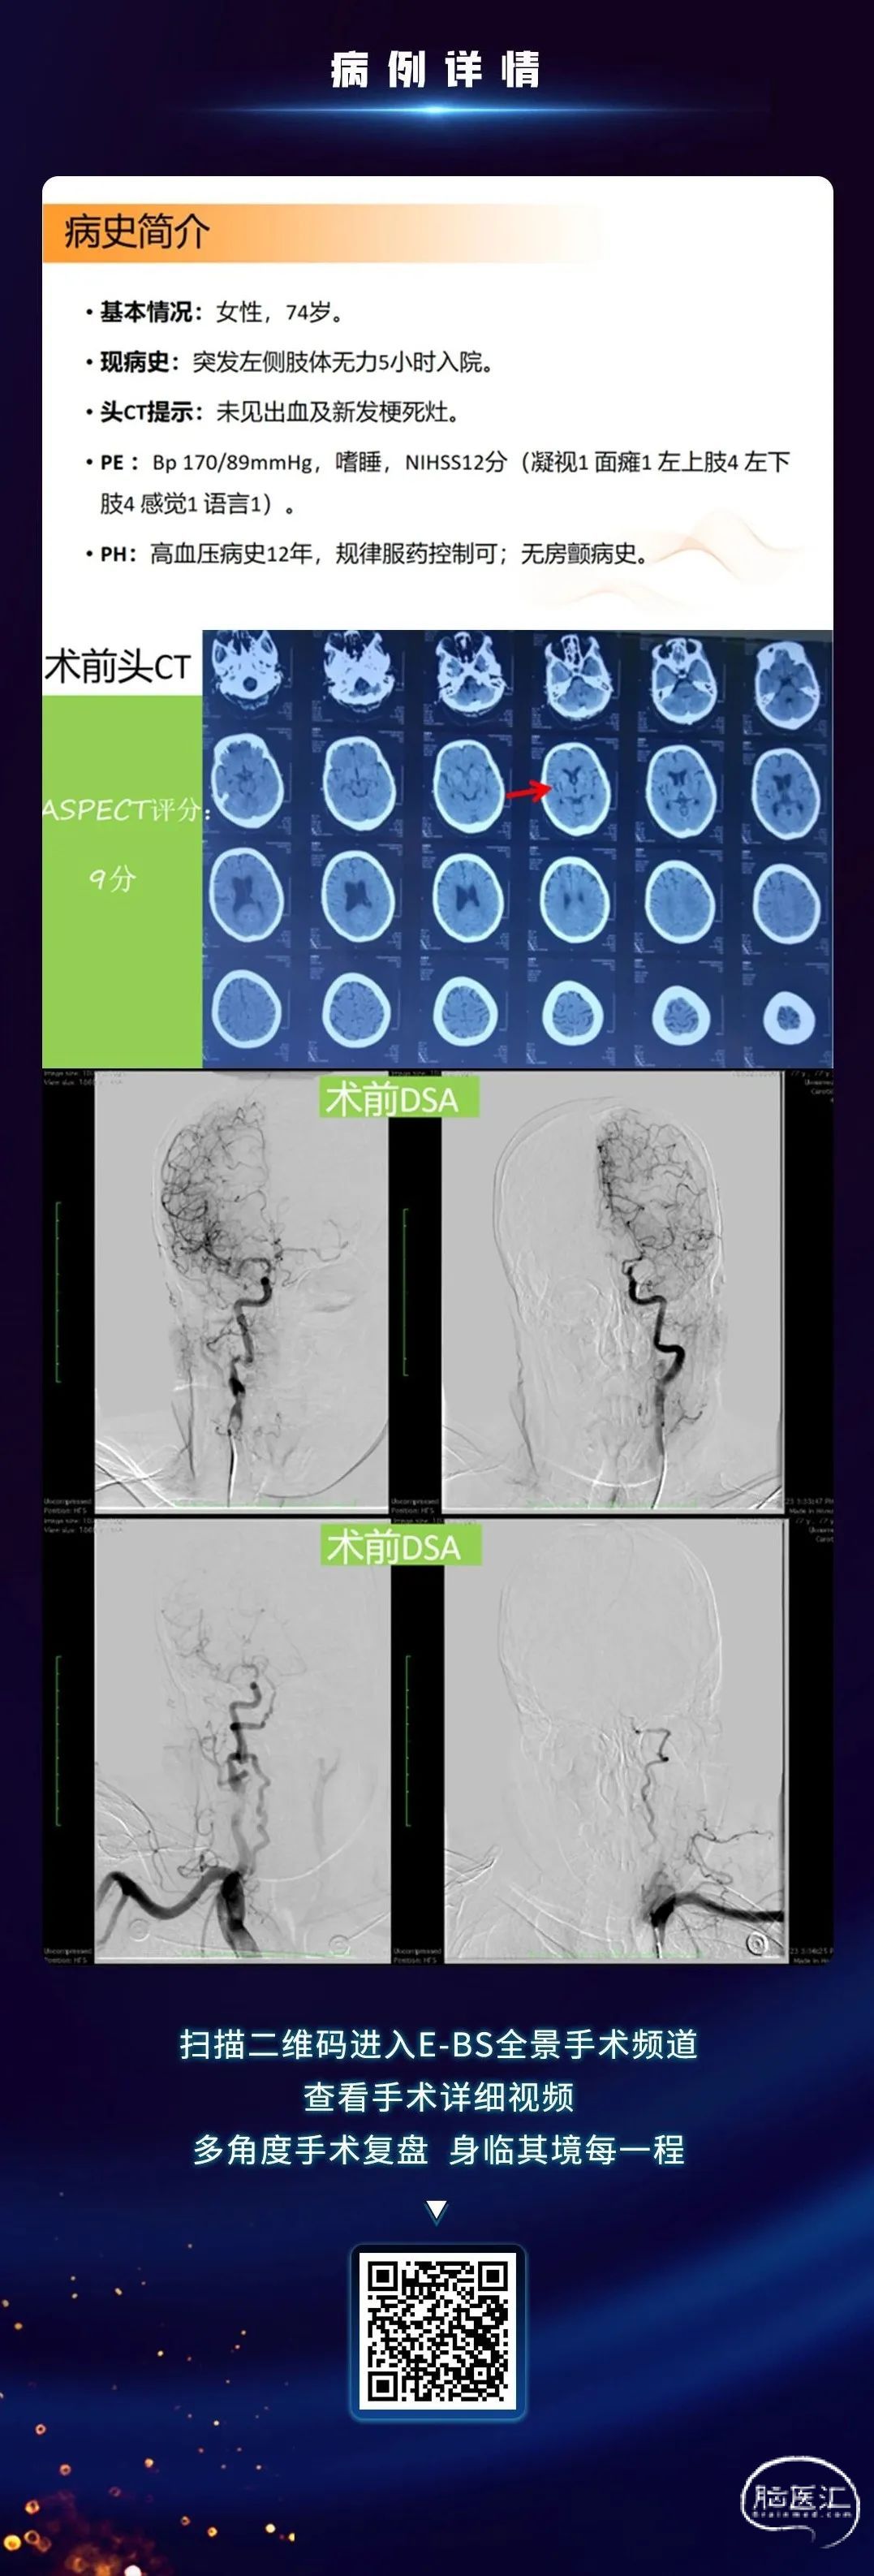

脑医汇-神介资讯平台携手石家庄市人民医院杨磊教授,为大家分享ICAS血管内介入治疗“零交换”技术,欢迎广大同道阅读、分享、交流!